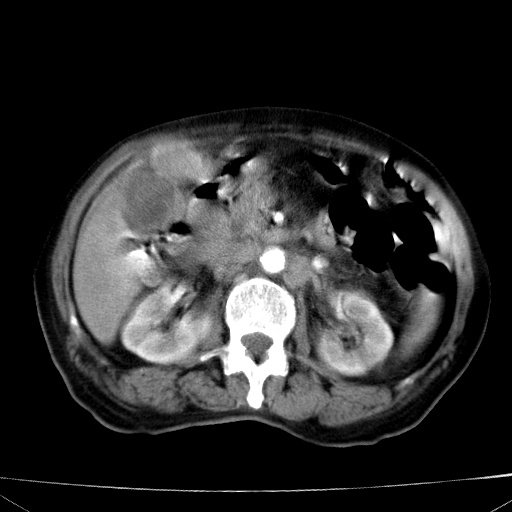

网站人气太旺!昨天的帖子就沉到海底,只好再发贴!ct18338:女 78岁,肝胆病变,已增强,再会诊!原帖链接:http://www.radida.com/bbs/forum.php?mod=viewthread&tid=50032

1)考虑胆囊癌侵犯肝脏并肝门区、腹膜后及右侧膈角后淋巴结转移。2)肝左叶近肝顶部囊肿。3)肝左叶肝内胆管结石。4)左肾近下极囊肿。

1、胆囊癌侵犯肝脏并腹腔及腹膜后淋巴结转移。

2、肝左叶外侧段囊肿。

3,肾囊肿